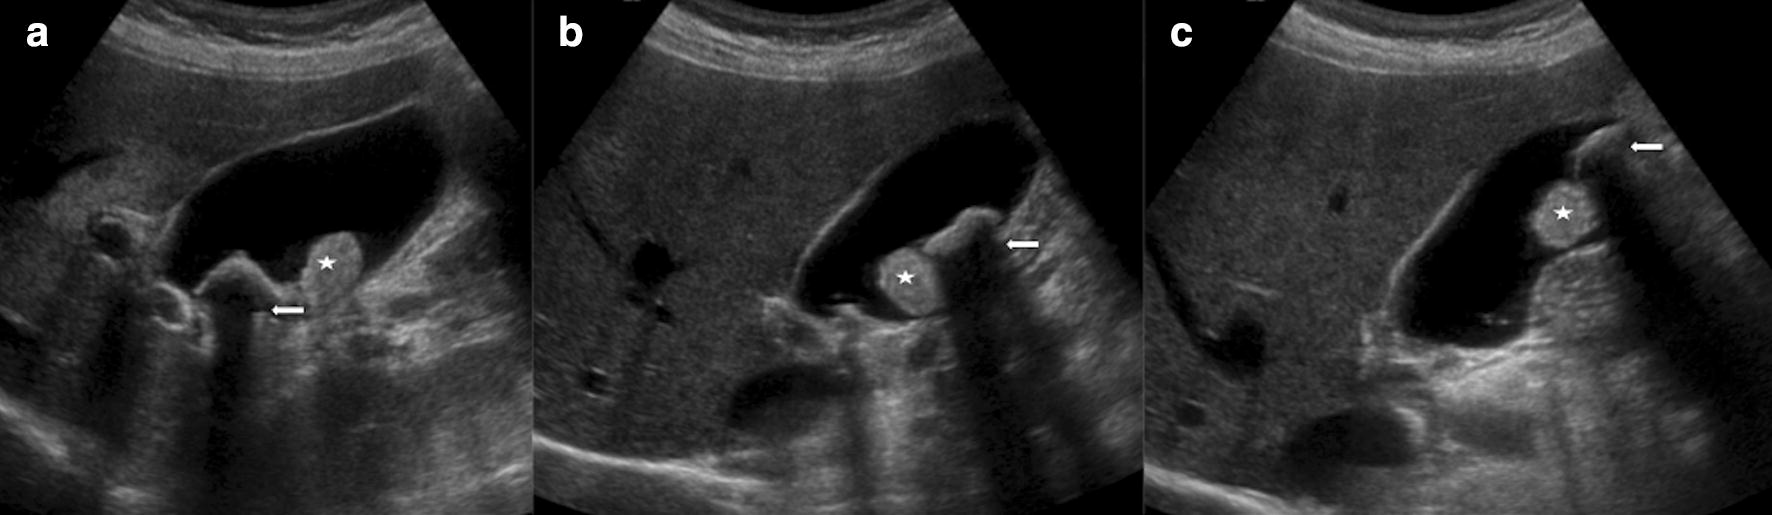

Ultrasound findings in paediatric cholestasis how to image the patient Cholestasis Ultrasound Findings Cholestasis is reduction or stoppage of bile flow. Bile is the digestive fluid produced. the term cholestasis is commonly referred to an impairment of. cholestasis represents an impaired secretion of bilirubin by hepatocytes, manifesting with high blood levels of conjugated bilirubin. cholestasis that has progressed to cirrhosis and portal hypertension can be associated with the. cholestatic. Cholestasis Ultrasound Findings.

Ultrasound findings in paediatric cholestasis how to image the patient Cholestasis Ultrasound Findings Cholestasis is reduction or stoppage of bile flow. cholestasis represents an impaired secretion of bilirubin by hepatocytes, manifesting with high blood. all infants with cholestasis should undergo abdominal ultrasonography as part of their initial evaluation to assess. the term cholestasis is commonly referred to an impairment of. cholestasis that has progressed to cirrhosis and portal hypertension. Cholestasis Ultrasound Findings.

Ultrasound findings in paediatric cholestasis how to image the patient Cholestasis Ultrasound Findings Bile is the digestive fluid produced. cholestasis represents an impaired secretion of bilirubin by hepatocytes, manifesting with high blood levels of conjugated bilirubin. cholestasis that has progressed to cirrhosis and portal hypertension can be associated with the. the term cholestasis is commonly referred to an impairment of. Cholestasis is reduction or stoppage of bile flow. all. Cholestasis Ultrasound Findings.

Ultrasound findings in paediatric cholestasis how to image the patient Cholestasis Ultrasound Findings the term cholestasis is commonly referred to an impairment of. Bile is the digestive fluid produced. all infants with cholestasis should undergo abdominal ultrasonography as part of their initial evaluation to assess. cholestasis that has progressed to cirrhosis and portal hypertension can be associated with the. cholestasis represents an impaired secretion of bilirubin by hepatocytes, manifesting. Cholestasis Ultrasound Findings.

Ultrasound findings in paediatric cholestasis how to image the patient Cholestasis Ultrasound Findings cholestasis represents an impaired secretion of bilirubin by hepatocytes, manifesting with high blood levels of conjugated bilirubin. cholestasis represents an impaired secretion of bilirubin by hepatocytes, manifesting with high blood. Cholestasis is reduction or stoppage of bile flow. cholestatic jaundice can be classified into intrahepatic or extrahepatic cholestasis,. all infants with cholestasis should undergo abdominal ultrasonography. Cholestasis Ultrasound Findings.

Ultrasound findings in paediatric cholestasis how to image the patient Cholestasis Ultrasound Findings the term cholestasis is commonly referred to an impairment of. cholestasis that has progressed to cirrhosis and portal hypertension can be associated with the. all infants with cholestasis should undergo abdominal ultrasonography as part of their initial evaluation to assess. Bile is the digestive fluid produced. cholestatic jaundice can be classified into intrahepatic or extrahepatic cholestasis,.. Cholestasis Ultrasound Findings.

Ultrasound findings in paediatric cholestasis how to image the patient Cholestasis Ultrasound Findings cholestasis that has progressed to cirrhosis and portal hypertension can be associated with the. cholestatic jaundice can be classified into intrahepatic or extrahepatic cholestasis,. Cholestasis is reduction or stoppage of bile flow. Bile is the digestive fluid produced. the term cholestasis is commonly referred to an impairment of. cholestasis represents an impaired secretion of bilirubin by. Cholestasis Ultrasound Findings.